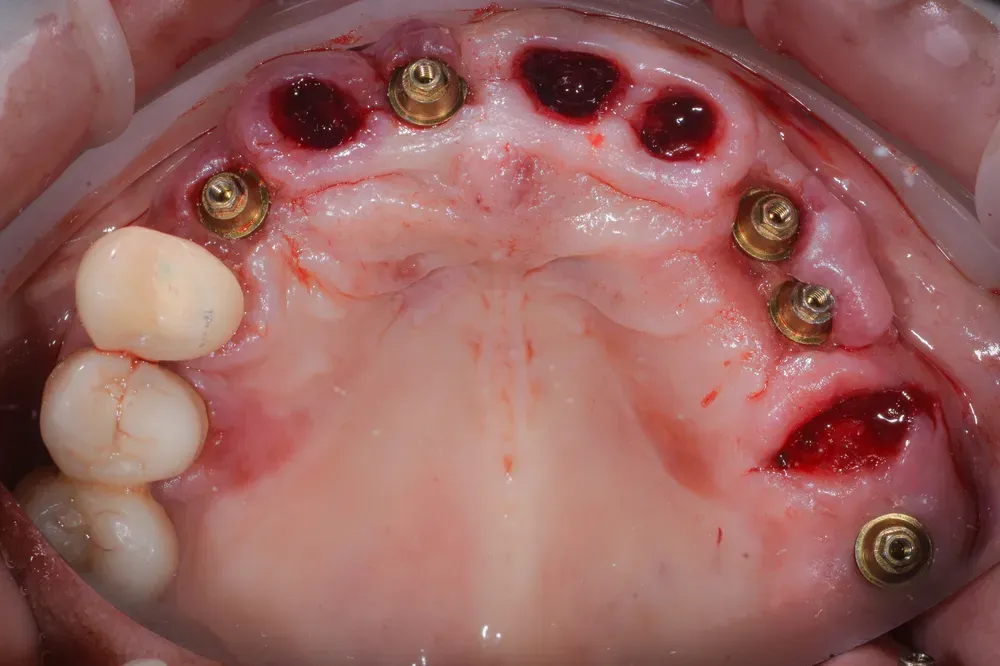

Altri impianti erano stati inseriti in modo errato ed erano in procinto di fallire per l’assenza di pareti ossee congrue (vedi figura sottostante).

Abbiamo rimosso facilmente i vecchi impianti, sostituendoli con nuovi. Ne abbiamo aggiunti altri, facendo innesti di osso eterologo e rialzo del seno mascellare, in considerazione del fatto che avremmo dovuto poi estrarre alcuni denti non mantenibili.

Nelle due figure sottostanti è evidente come la terapia, qui ancora in fase di estrazione dei denti non mantenibili, ottenga il ripristino totale (la rigenerazione) del tessuto alveolare e quindi una forma del tutto simile a quella naturale. E questo si ottiene solo con l’espansione mucosa del sito e senza xenoinnesti di connettivo. Inoltre, nei siti (alveoli) estrattivi non è stato inserito nulla per mantenere la forma: il mantenimento si ottiene solo con la forma del provvisorio che si inserisce per 4 mm all’interno con i “ponti ovoidi”.